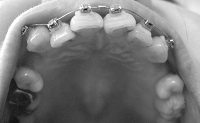

そんなわけで、ここんとこ変化がなくて寂しいので、この7ヶ月の変化が分かるように写真を並べて自分を励ますことにします~

ねね、全然違いますよね!!

正面から見たところなんて、こうやって見ると別人ですよね。